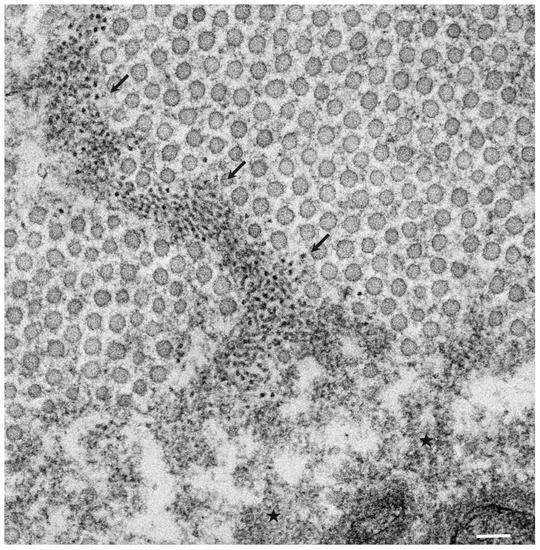

- Koike, H.; Katsuno, M. The Ultrastructure of Tissue Damage by Amyloid Fibrils. Molecules 2021, 26, 4611. [Google Scholar] [CrossRef] [PubMed]

- Koike, H.; Nishi, R.; Ikeda, S.; Kawagashira, Y.; Iijima, M.; Sakurai, T.; Shimohata, T.; Katsuno, M.; Sobue, G. The morphology of amyloid fibrils and their impact on tissue damage in hereditary transthyretin amyloidosis: An ultrastructural study. J. Neurol. Sci. 2018, 394, 99–106. [Google Scholar] [CrossRef] [PubMed]

- Koike, H.; Mouri, N.; Fukami, Y.; Iijima, M.; Matsuo, K.; Yagi, N.; Saito, A.; Nakamura, H.; Takahashi, K.; Nakae, Y.; et al. Two distinct mechanisms of neuropathy in immunoglobulin light chain (AL) amyloidosis. J. Neurol. Sci. 2021, 421, 117305. [Google Scholar] [CrossRef] [PubMed]